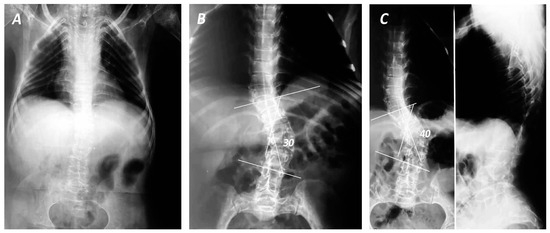

Figure 1. Anteroposterior (AC) and lateral (C) views of total spine in standing position of a female patient with OI after 30 years of follow-up. Although during childhood the patient presented mild scoliosis (A), the deformity progressed rapidly during the last 5 years of follow-up (B,C), demonstrating right thoracolumbar curves (Lenke V) of 30 (B) and 40 degrees between 11th thoracic (T11) and 4th lumbar (L4) with apex in 2nd Lumbar (L2) vertebrae (C).

Although the age of onset of spinal deformities varies in international literature, ranging from 2 to 65 years [4], it is documented that curve progression is observed after the 5th year of age (Figure 1), and it worsens when the Cobb angle exceeds 50 degrees. This notion was corroborated by the study of Norimatsu et al. [34], which identified rapid progression of spinal deformities in patients with the congenital type of OI after the age of five, reaching peak severity at approximately 12 years of age. In the same study, scoliotic deformities in patients with the tarda type of OI developed gradually; however, a rapid deterioration was observed once the curve exceeded 50 degrees, with the curvature potentially escalating to more than 100 degrees [34]. The anatomical location and severity of the scoliotic curvatures were also associated with disease severity, as a cross-sectional study of 102 OI patients demonstrated that the prevalence of scoliosis was 74.5%, with a mild curvature of <40 degrees in 56 patients, moderate of <60 degrees, severe of <80 degrees and a very severe deformity of >80 degrees in 8, 7 and 5 patients, respectively [16]. The above study detected that the average expansion concerned 6.7 vertebrae (3–12), accompanied by an average rotation of 2 (1–4) [16]. These results were in line with the study of Watanabe et al. [32], which reported an average Cobb angle of 25.2 degrees (ranging from 5 to 108 degrees).